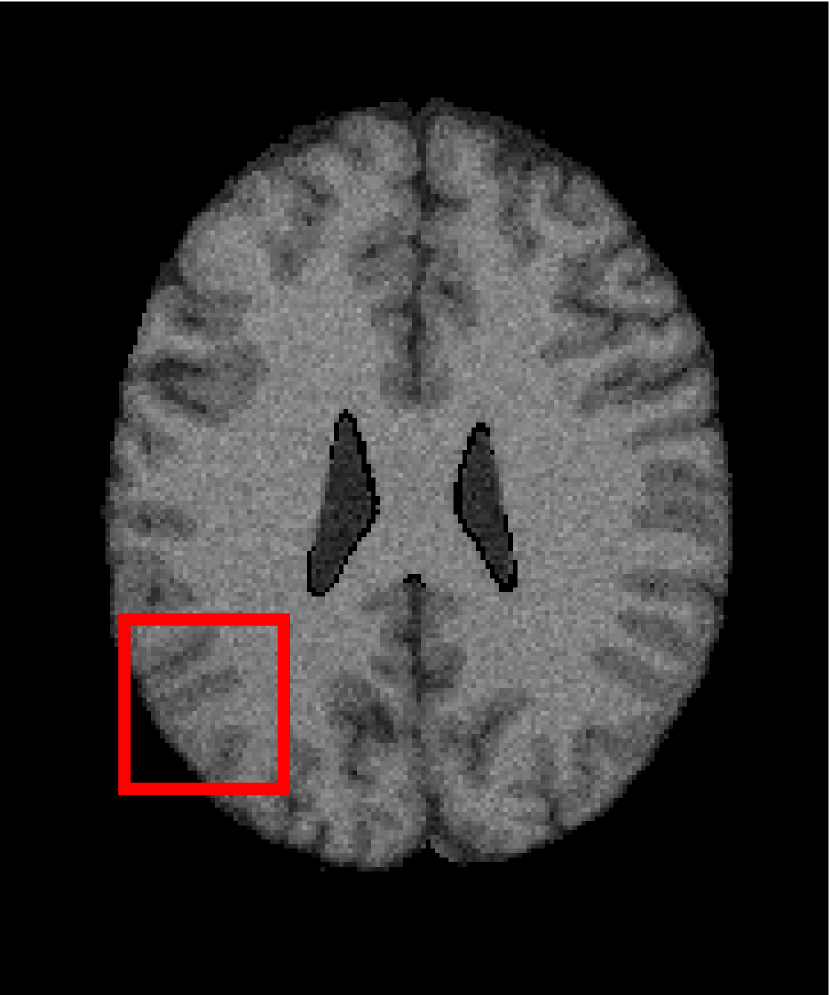

In the second experiments, we segment two medical images coming from a simulated brain database (BrianWeb): http://www.bic.mni.mcgill.ca/brainweb/. The two images are generated by T1 modality with slice thickness of 1mm resolution, 9% noise and 20% intensity non-uniformity. Here, the two images are represented two slices in the axial plane with the sequence of 100 and 110. Moreover, there are golden standard segmentations in the dataset. We set the numbers of clusters to 4. The visual comparisons are illustrated in Figs. 6 and 7.

Figure 7: Segmentation results for the second medical image. From (a) to (l): ground truth, noisy image and results of FCM_S1, FCM_S2, FGFCM, FLICM, KWFLICM, ARKFCM, FRFCM, WFCM, DSFCM_N, and LRFCM.

By focusing on the marked red square in Figs. 6 and 7, we easily find that FCM_S1, FCM_S2, FGFCM and ARKFCM are sensitive to noise. FLICM and KWFLICM are vulnerable to severe intensity inhomogeneity. FRFCM brings overly smooth results due to the use of gray level histograms. WFCM and DSFCM_N cause several contours to change. However, LRFCM acquires clear contours and suppresses noise adequately. Moreover, we find that the segmentation result of LRFCM is closer to ground truth.